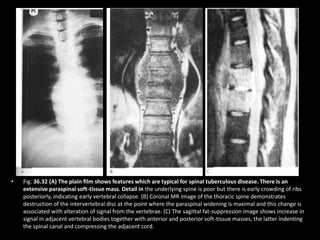

• Fig. 36.32 (A) The plain film shows features which are typical for spinal tuberculous disease. There is an

extensive paraspinal soft-tissue mass. Detail in the underlying spine is poor but there is early crowding of ribs

posteriorly, indicating early vertebral collapse. (B) Coronal MR image of the thoracic spine demonstrates

destruction of the intervertebral disc at the point where the paraspinal widening is maximal and this change is

associated with alteration of signal from the vertebrae. (C) The sagittal fat-suppression image shows increase in

signal in adjacent vertebral bodies together with anterior and posterior soft-tissue masses, the latter indenting

the spinal canal and compressing the adjacent cord.

• Fig. 36.32(A) The plain film shows features which are typical for spinal tuberculous disease. There is an extensive paraspinal soft-tissue mass. Detail in the underlying spine is poor but there is early crowding of ribs posteriorly, indicating early vertebral collapse. (B) Coronal MR image of the thoracic spine demonstrates destruction of the intervertebral disc at the point where the paraspinal widening is maximal and this change is associated with alteration of signal from the vertebrae. (C) The sagittal fat-suppression image shows increase in signal in adjacent vertebral bodies together with anterior and posterior soft-tissue masses, the latter indenting the spinal canal and compressing the adjacent cord.